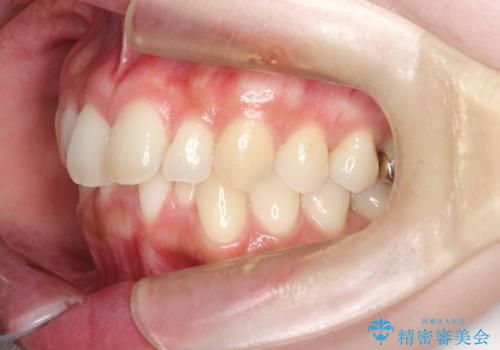

インビザラインで整えた前歯の歯並び

- 患者様は、上下前歯の歯列不正(ガタガタ)を主訴としてご来院されました。治療計画として、透明なマウスピース型矯正装置「インビザライン」を使用し、約2年の期間を見込んで前歯部の歯列を整える方針を立てました。特に下顎前歯に歯肉退縮のリスクがあるため、治療中にIPR(インタープロキシマルリダクション)を行い、歯間を適切に削ることで、過度な圧力を避け、歯肉退縮を防ぎながら配列を進めました。治療は慎重に進め、最終的にきれいで整った前歯の歯並びを目指しました。

インビザラインによる矯正治療は、患者様自身が装着するマウスピース型の装置を使用するため、装着時間の徹底が重要です。特に、下顎前歯の歯肉退縮を避けるため、IPRを施すことで歯間スペースを確保し、歯肉にかかる負担を減らしました。この方法により、歯並びを整えながらも歯肉の健康を保つことができます。治療期間中は定期的にチェックを行い、歯肉の状態や歯の動きを慎重に確認しました。また、治療後はリテーナーを装着して歯並びを維持し、安定させました。